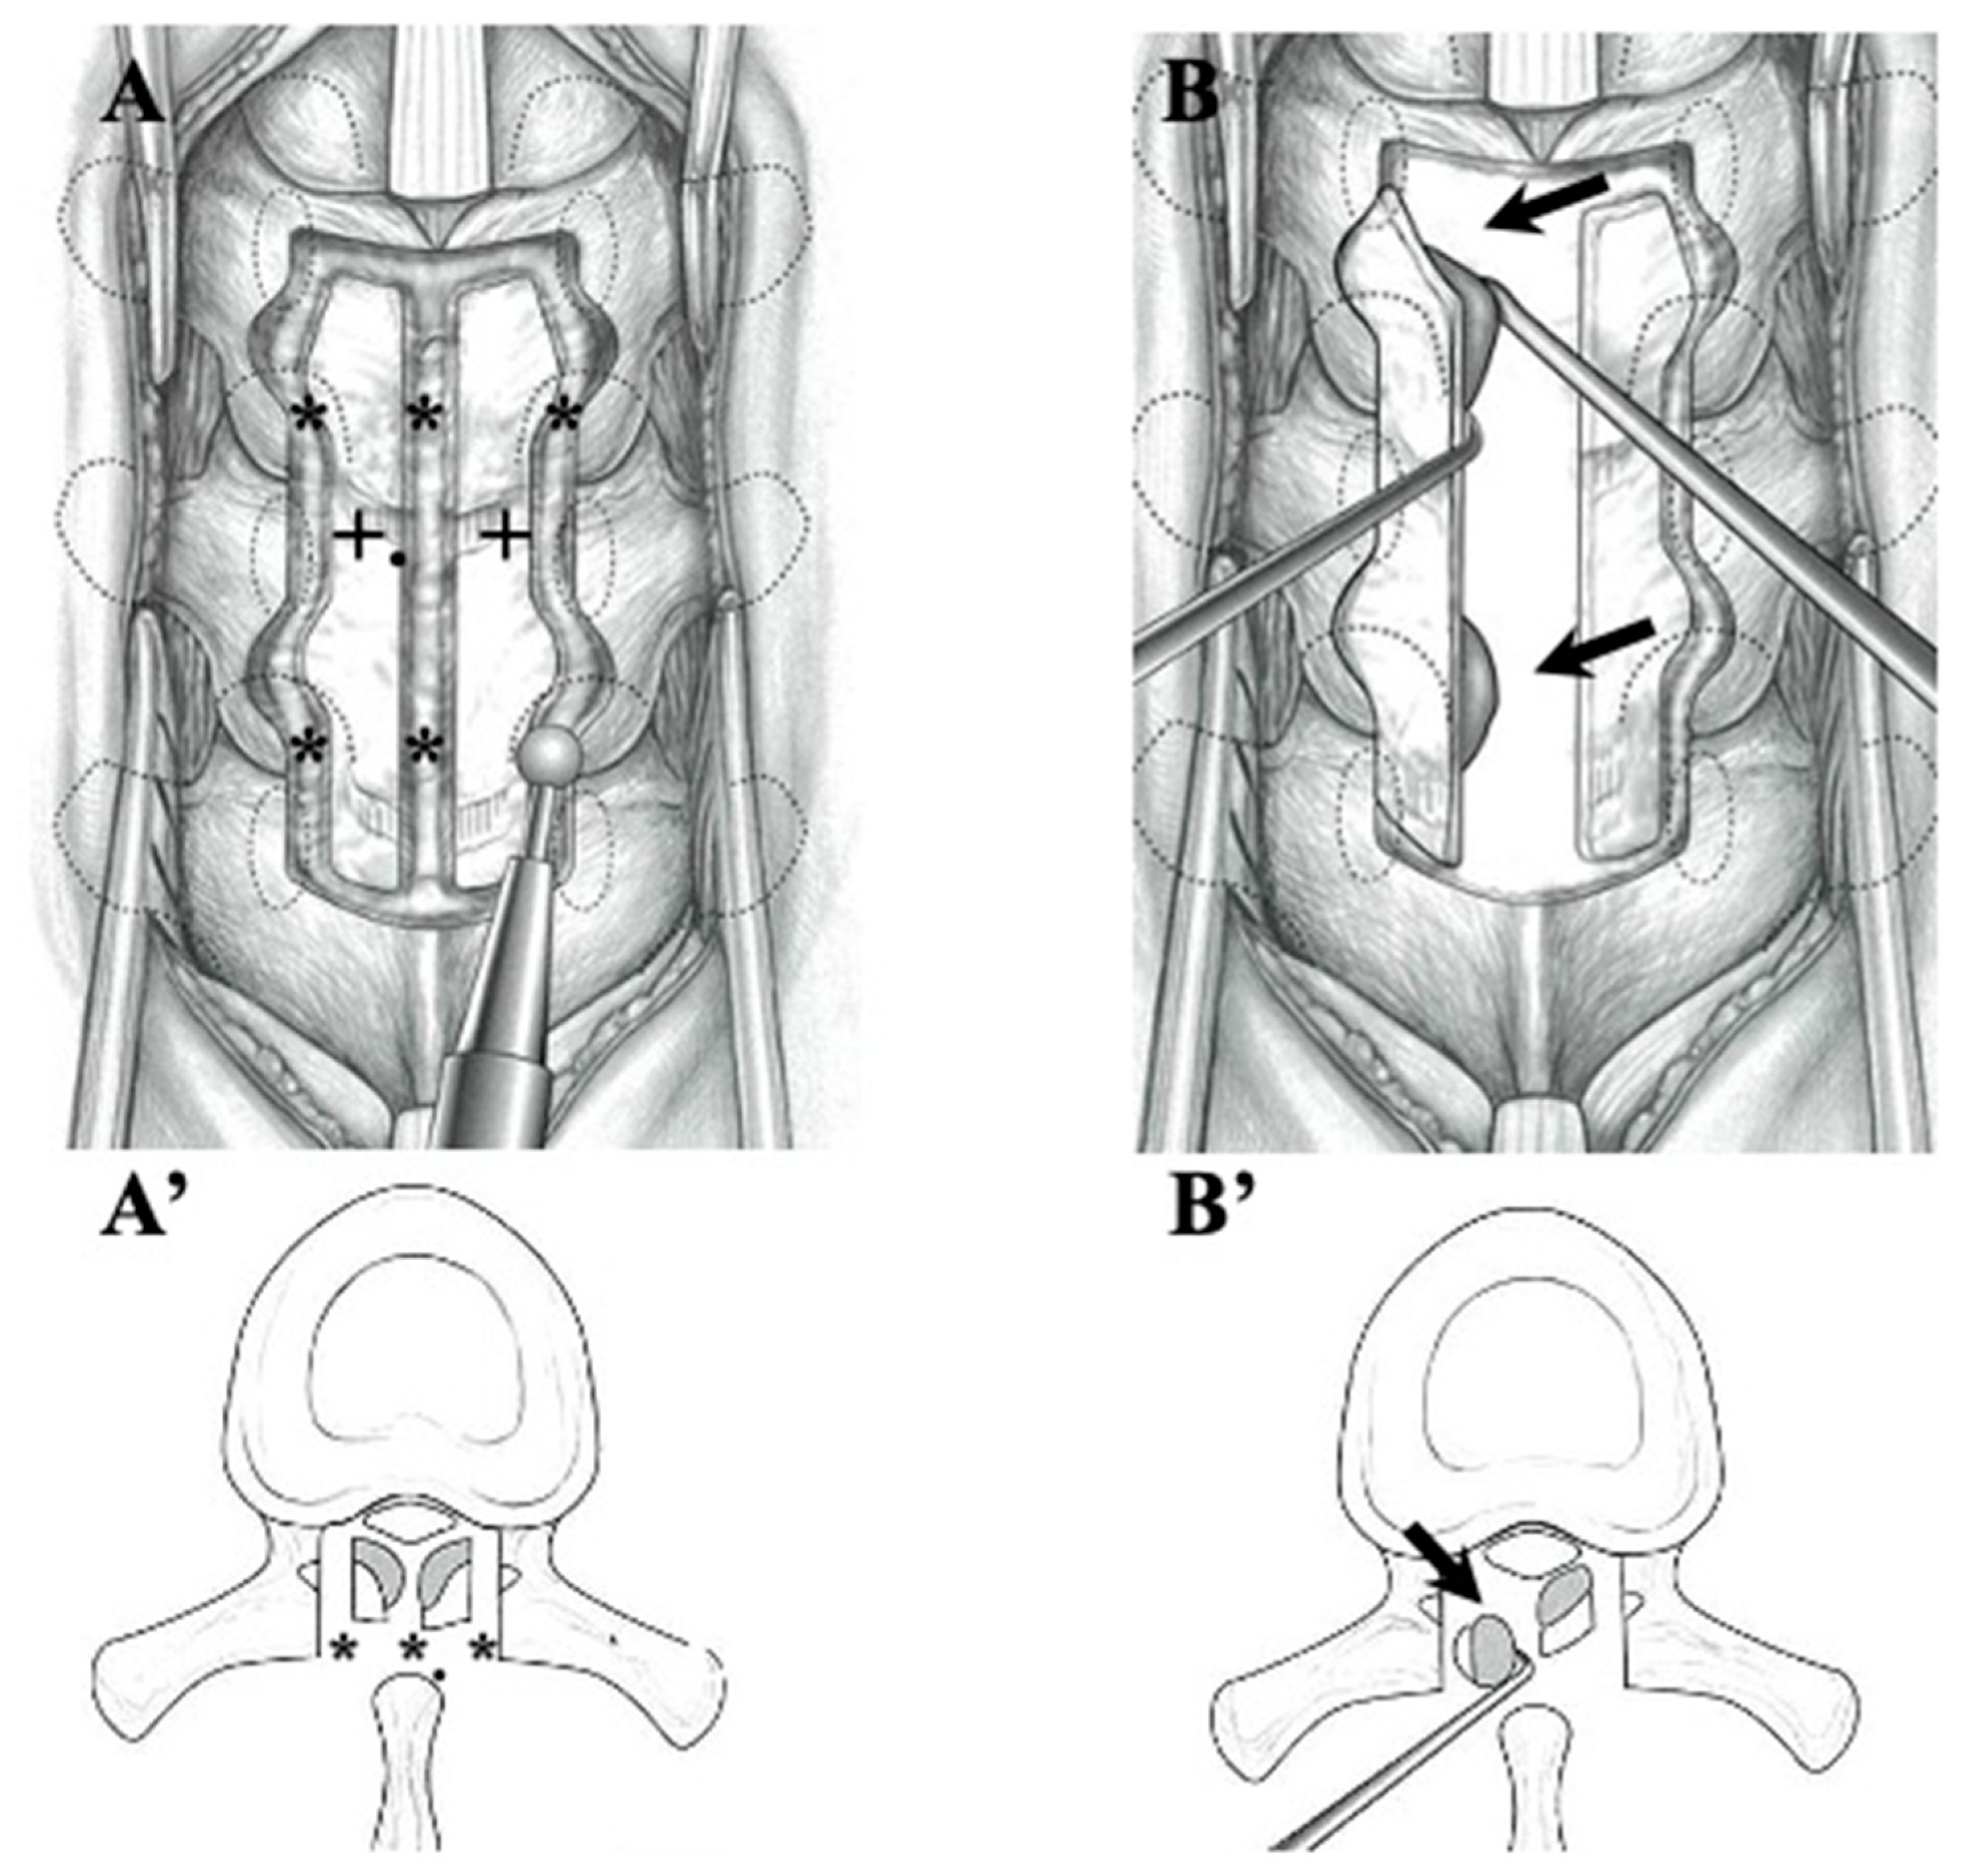

2.2.2. Surgical Indication and Procedure (Figure 1 and Figure 2, Table 4)

4.3. Surgical Treatments and Outcomes in CLF and OLF (Figure 1 and Figure 2; Table 4)